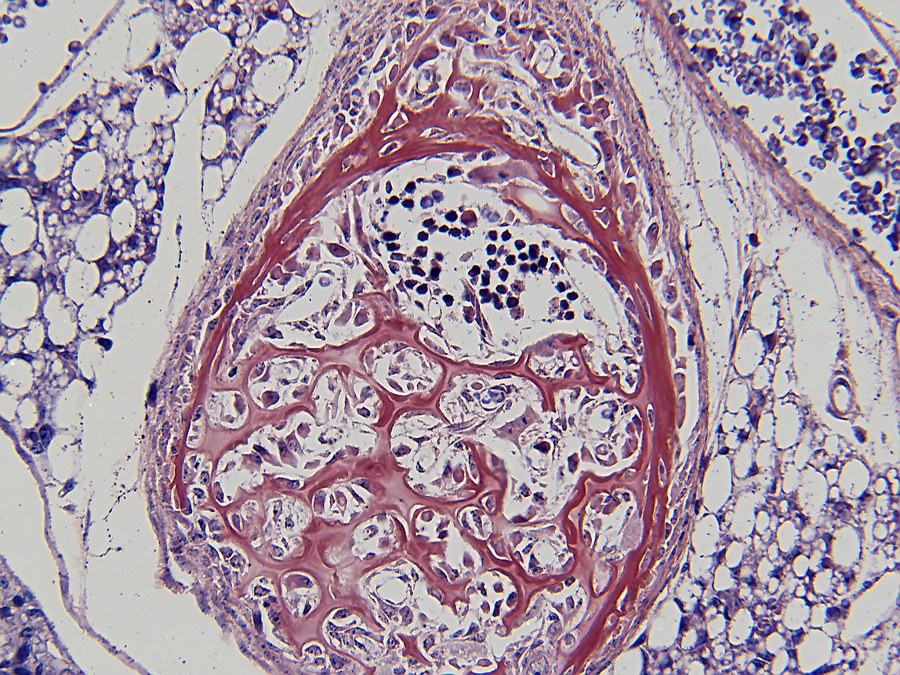

Bone formation or ossification[2] visualized by various histological stains.

In both cases, primary (braided or plexiform) bone is first formed, which is soon replaced by secondary (lamellar) bone, which may have a compact or spongy appearance macroscopically. During bone growth, areas of primary bone, bone breakdown, and secondary bone continually occur side by side. This coexistence of breakdown and creation (remodeling) continues in the adult body, although at a much slower rate.

Bone is composed of cells and intercellular material that is calcified, the bone or bone matrix. Three types of cells can be distinguished:

1. Osteoblasts (bone forming cells), which produce the organic components of the bone matrix. Osteoblasts arise from osteoprogenitor cells, which are found in endosteum[2] and periosteum[2]. Osteoblasts synthesize the organic components of the bone matrix and thus produce collagen type I, proteoglycans[2] and glycoproteins[2]. Osteoblasts are located in contiguous rows, the osteoblast hemisphere, against the surface of the bone;

2. Osteocytes (mature bone cells) formed by maturation of osteoblasts lie in cavities (lacunae) of the bone matrix. From these cavities, canaliculi run through the bone in different directions, containing the outgrowths of osteocytes. They make contact with each other through gap junctions[2], allowing the exchange of ions and small molecules;

3. Osteoclasts (bone-degrading cells); these are large multinucleated (up to fifty nuclei) cells that can break down bone. Osteoclasts are freely motile cells and lie as elongated cells against the bone margin, sometimes in a hollow created by them eating away matrix: the lacuna of Howship.

To observe the staining of bone forming tissue and the differences in staining, it was chosen to cut sections of similar tissue which was fixed in the same way. For this purpose, five-day-old mice were fixed in Bouin liquid. To allow the fixative to penetrate the tissue more easily, the extremities were removed and small incisions were made in the skin. Tissue was left in Bouin for approximately two months after which dehydration was started in ethanol 70%. The usual rinsing out of the fixative in water did not take place to prevent tissue from swelling too much[3]. Further ethanol steps were 85%, 95% and 100% with a duration of 48 hours per step. Via xylene, the switch to paraplast plus was then made. To ensure that all xylene was replaced with paraplast, three liquid paraplast baths were used.

Tissue was then cut on an A&O 820 rotary microtome with Leica 818 high profile microtome blades. After drying, the paraplast was removed via 2 xylene baths and the sections hydrated in an ethanol series of 100%, 95%, 85%, 70% and 50%. Staining which was performed were:

- Haematoxylin/Eosin[8];